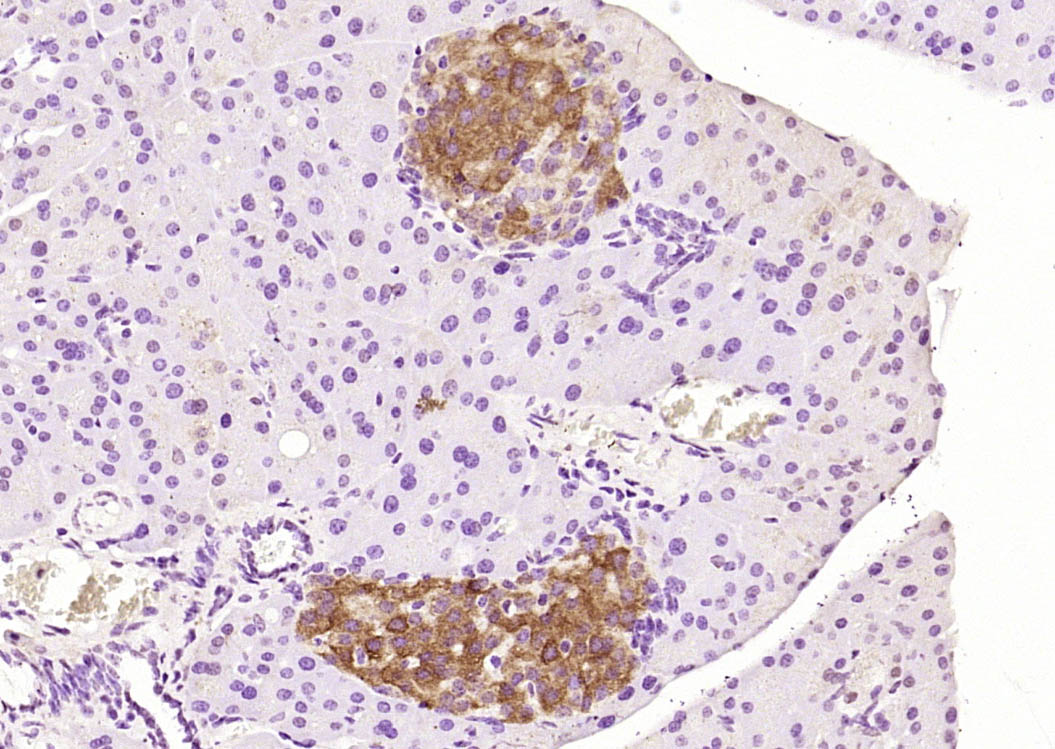

| IHC-P | Human, Mouse, Rat | Pig, Cow, Dog, Horse | 1:100-500 |